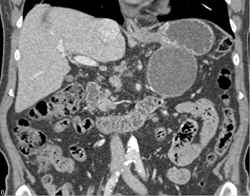

Huge Varices With Splenorenal Shunts Simulates Adenopathy